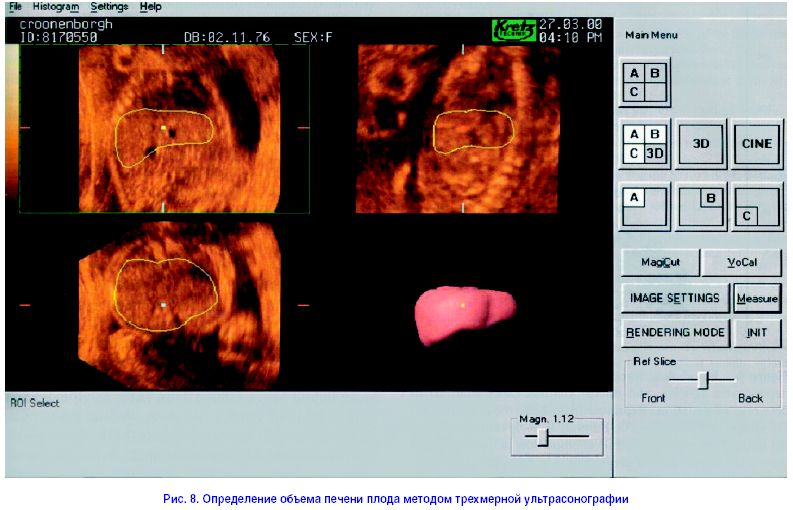

На рис. 8 приведены результаты недавно проведенного внутриутробного определения объема печени плода методом трехмерной ультрасонографии. По результатам, полученным с помощью данного метода, увеличение объема печени у здоровых плодов с 18 недели беременности до момента родов описывается экспоненциальным графиком [7]. В то же время получено подтверждение того, что патология плода, ведущая к нарушению его роста, ассоциируется с пропорционалными изменениями объема его печени, уменьшение и увеличение которого было отмечено при IUGR и инсулинзависимом сахарном диабете соответственно [8].